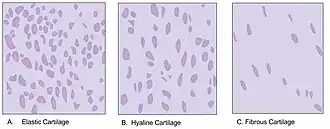

Cartilage

Cartilage is a resilient and smooth type of connective tissue. Semi-transparent and non-porous, it is usually covered by a tough and fibrous membrane called perichondrium. In tetrapods, it covers and protects the ends of long bones at the joints as articular cartilage,[1] and is a structural component of many body parts including the rib cage, the neck and the bronchial tubes, and the intervertebral discs. In other taxa, such as chondrichthyans and cyclostomes, it constitutes a much greater proportion of the skeleton.[2] It is not as hard and rigid as bone, but it is much stiffer and much less flexible than muscle or tendon. The matrix of cartilage is made up of glycosaminoglycans, proteoglycans, collagen fibers and, sometimes, elastin. It usually grows quicker than bone.

Cartilage is composed of specialized cells called chondrocytes that produce a large amount of collagenous extracellular matrix, abundant ground substance that is rich in proteoglycan and elastin fibers. Cartilage is classified into three types — elastic cartilage, hyaline cartilage, and fibrocartilage — which differ in their relative amounts of collagen and proteoglycan.